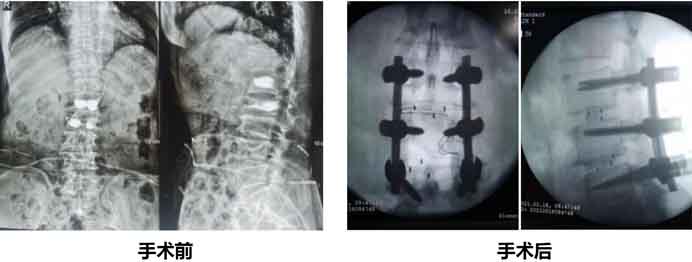

3月11日,付阿姨慕名來(lái)到嘉興邦爾骨科醫(yī)院,告訴醫(yī)生,“3年來(lái)曾多次脊柱骨折,導(dǎo)致腰背后凸起,做過(guò)兩次椎體成形手術(shù)。1年前勞累后突然疼痛難忍,當(dāng)時(shí)并沒(méi)有太在意,但是最近這一周腰臀部陸續(xù)感覺(jué)劇烈疼痛,活動(dòng)受限,晚上睡覺(jué)也睡不安穩(wěn)”。付阿姨通過(guò)檢查后,以1、外傷性脊柱后凸 2、腰椎椎管狹窄收入。趙凱院長(zhǎng)和骨科朱科林主任立即展開(kāi)討論,最后為付阿姨制定手術(shù)方案——“智微天眼骨科機(jī)器人”輔助下完成“胸腰椎后路截骨矯行+減壓融合內(nèi)固定術(shù)”。

今天是手術(shù)后的第四天,朱主任查房時(shí)表示:付阿姨狀態(tài)非常好,術(shù)后出血很少,幾乎無(wú)痛感,下肢運(yùn)動(dòng)感覺(jué)功能正常。